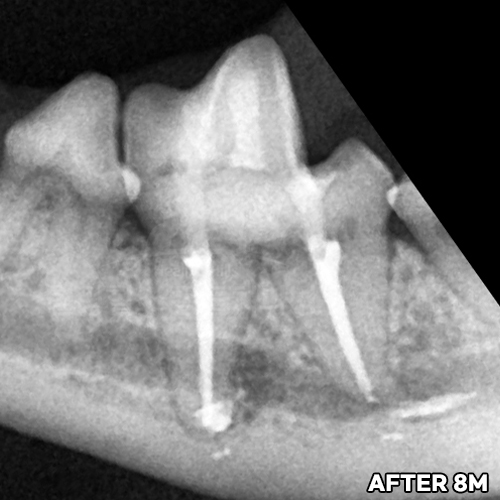

턱뼈 부러뜨리는 강아지치근단농양! 2.3kg 초소형견 발치하지 않고 신경치료하여 자기치아 살리는 힐링힐스